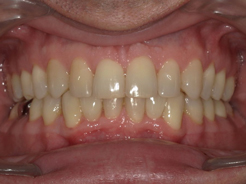

Présentation cas n°1 :

Présentation cas n°2 :